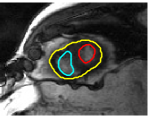

The problem above is a generalization of Horn & Schunck optical flow. Note that solving for the Horn & Schunck optical flow within each region separately does not lead to motions such that at the interface, they have equal normal components (see Figure 1), whereas the solution of (5) to be presented in subsequent sections does. Note that computing Horn & Schunck optical flow in each region requires boundary conditions (and typically they are chosen to be Neumann boundary conditions: and on ). Note that replacing these boundary conditions with the boundary constraint (6) does not specify a unique solution. Also, while Horn & Schunck optical flow computed on the whole domain naturally gives a globally smooth motion, which by default satisfies matching normals at the interface, this is not natural for the ventricles / myocardium, where different motions exist in the regions (see Figure 2), and the motions should not be smoothed across the regions.

![]() |

| image + boundary | next image | within region optical flow | our method |